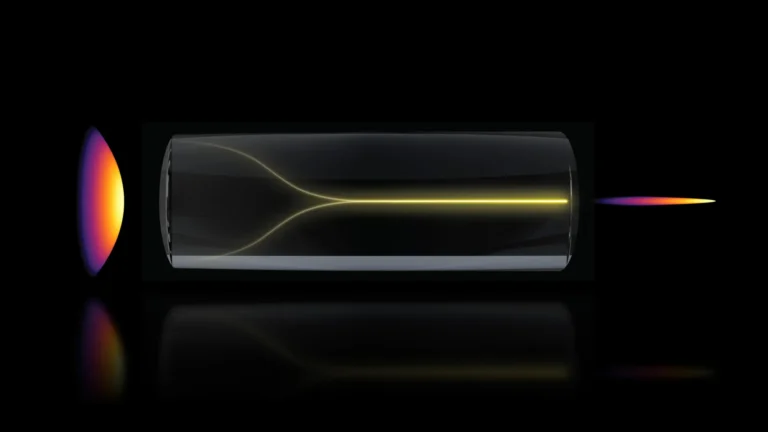

In an endeavor to foster a more profound understanding of these complex interactions, the research team meticulously analyzed a substantial dataset drawn from the UK Biobank, encompassing the participation of nearly 125,000 women. The cohort was strategically categorized into three distinct groups: premenopausal women, postmenopausal women who had never undergone HRT, and postmenopausal women who had received HRT. Participants meticulously completed a battery of questionnaires designed to assess various facets of their health, including the subjective experience of menopausal symptoms, their mental health status, established sleep patterns, and general health indicators. A subset of these participants also undertook standardized cognitive assessments to evaluate memory function and reaction times. Furthermore, approximately 11,000 women underwent advanced magnetic resonance imaging (MRI) scans, providing researchers with an invaluable opportunity to scrutinize structural differences within the brain. The average age at which participants experienced menopause was approximately 49.5 years, with those prescribed HRT typically initiating treatment around the age of 49.

The neuroimaging data revealed a significant reduction in grey matter volume among postmenopausal women, a phenomenon observed irrespective of their HRT utilization. Grey matter, the brain’s primary locus for processing information, orchestrating motor control, and underpinning memory formation and emotional regulation, plays a pivotal role in numerous cognitive functions. The regions exhibiting the most pronounced volumetric changes included the hippocampus, a brain structure critically involved in the consolidation and retrieval of memories; the entorhinal cortex, which serves as a crucial gateway for information transfer between the hippocampus and other cortical areas; and the anterior cingulate cortex, a key component of the brain’s executive functions, instrumental in emotion regulation, decision-making, and attentional control.

These observed neurological alterations may hold significant implications for understanding women’s long-term brain health, particularly concerning their predisposition to neurodegenerative diseases. Professor Barbara Sahakian, the senior author of the study from the Department of Psychiatry, pointed out that the brain regions identified as showing these differences are notably those typically affected by Alzheimer’s disease. She suggested that menopause could potentially render these women more vulnerable to such conditions later in life. While acknowledging that menopause is not the sole determinant, she posited that these findings might contribute to explaining the observed disparity in dementia prevalence, where women are diagnosed with the condition at nearly twice the rate of men.